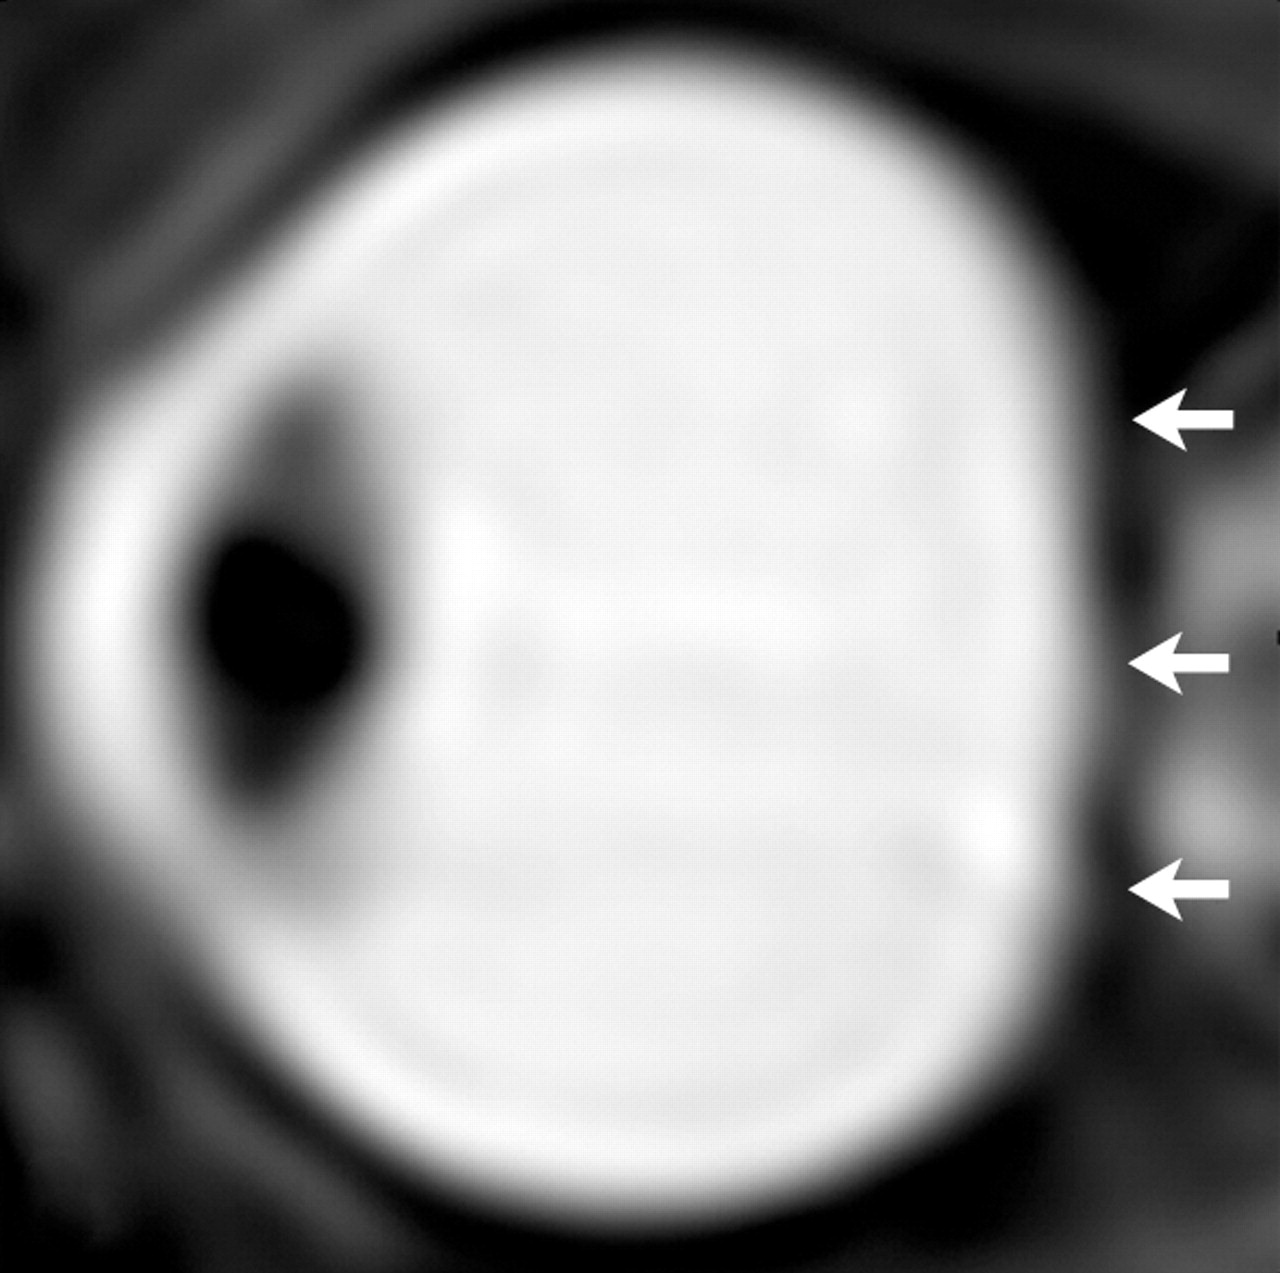

L’occhio destro di un astronauta. Dopo la lunga esposizione alla microgravità, dagli esami sono emersi l’appiattimento del globo posteriore (frecce corte) e la deviazione della guaina del nervo ottico. Crediti: Radiological Society of North America

Per lo studio sistematico di questa patologia, si è partiti dalle risonanze magnetiche pre e post volo del cervello e dell’orbita oculare di sette astronauti di missioni di lunga durata sulla ISS e di nove astronauti della missione di breve durata sullo Space Shuttle. Dopo avere accuratamente confrontato i dati, sono emersi chiaramente i sintomi: appiattimento del globo oculare e protrusione del nervo ottico in associazione con aumenti di volume del liquido cerebrospinale infraorbitale, del liquor ventricolare e del liquido interstiziale del tessuto cerebrale. Dai test si evince che gli astronauti delle missioni di lunga durata presentano i cambiamenti più gravi, ma non ci sono stati significativi cambiamenti post-volo nel volume della materia grigia o nel volume della materia bianca in entrambi i gruppi di astronauti.